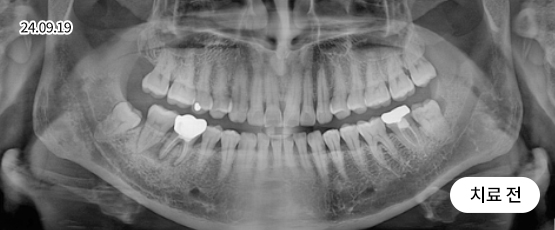

치아의 정출 + 임플란트

정출된 치아에 그냥 심으면 안됩니다.

치아가 소실된 상태로 오래 방치하면, 치아가 아래로 내려오거나 위로 솟구칠 수 있는데, 이를 정출이라고 부릅니다.

정출된 치아를 그대로 두고 임플란트를 심으면 치아 대합이 맞지 않고 환자에게 올바른 치료가 될 수 없기 때문에

임플란트 치료와 더불어 치아교정 또는 크라운 등의 보철치료를 할 수 있습니다.